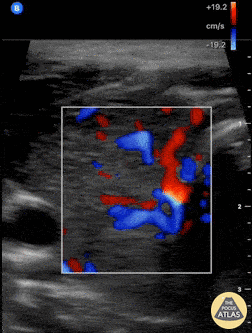

Soft Tissue - Thyroid Inferno

A patient with impending thyroid storm (BWPS score 25), an undetectable TSH level, and a T4- 4.2, had diffusely enlarged goiter. POCUS as shown here revealed hypervascular “thyroid inferno” that occurs in Graves disease, less commonly Hashimoto’s thyroiditis. Shane Solger